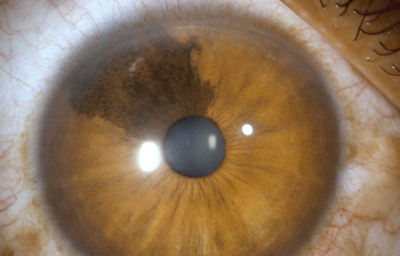

Melanocitosis Ocular unilateral ( Melanosis ocular) Es una heterocromía unilateral con hiperpigmentación, puede verse en los nevus de Iris; cuando la hiperpigmentación compromete la esclera y la piel periocular, se la conoce como nevus de Ota; se debe hacer diagnóstico diferencial con Melanocitoma y con Melanoma Difuso del Iris

Melanocitosis Ocular

Archivo fotográfico Dr. Carmen Barraquer.

Melanocitosis Ocular

Archivo fotográfico Dr. Francisco Barraquer.